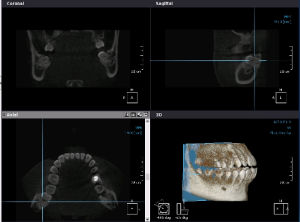

口腔三合一CT3D口腔CT成像的直接套用,為牙齒種植領域邁進革命性一步。種植手術的成功率,與病人牙床的骨質密度、牙槽骨本身的高度、寬度等條件息息相關,種植手術時,植體要植入的位置及骨骼狀況,種植醫生都須仰賴精準的儀器(CT)與純熟的技術來做判斷,結合歐美全新“親骨”無痛種植技術確保手術的成功率。

親骨技術示意圖